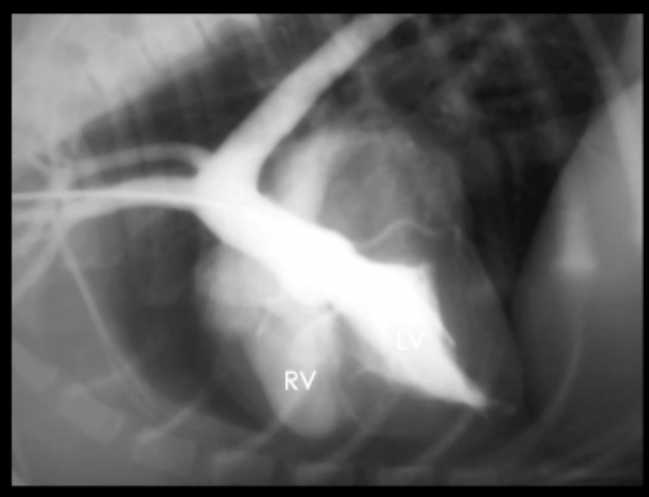

What can be seen in this angiogram?

ventricular septal defect